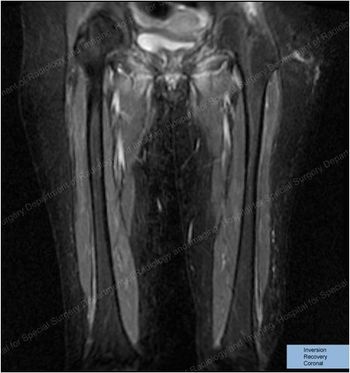

She presented with such severe calf pain she could no longer walk unassisted, with a months-long history of fever of unknown origin. What does the MRI show?

This young woman presented with severe leg pain, night sweats, and fever of unknown origin. The diagnosis of polyarteritis nodosa had several unusual features.